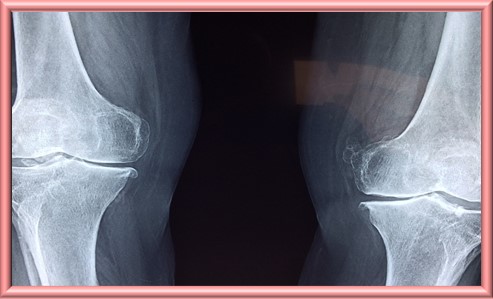

12. 뼈 약화

신장은 비타민 D를 활성화하여 뼈 건강을 유지하는 데 중요한 역할을 한다. 신장 기능이 저하되면 비타민 D 결핍 때문에 칼슘 흡수가 감소하고 뼈가 약해져 골다공증이나 뼈 통증이 발생할 수 있다.